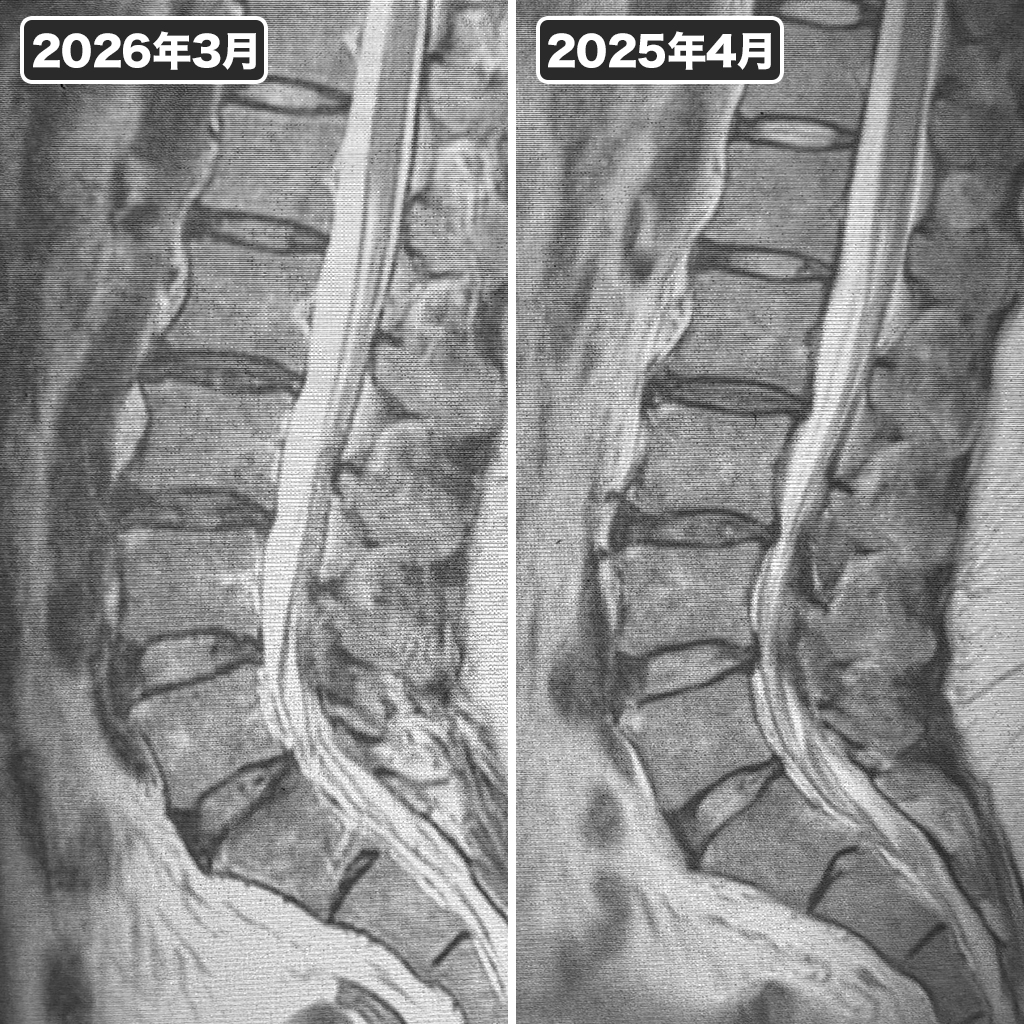

MRI検査(腰椎)

右側が2025年4月の腰椎MRIで、左側が2026年3月の腰椎MRI検査です。椎間板損傷部分の改善などが確認出来ます。腰の調子は良いようです。